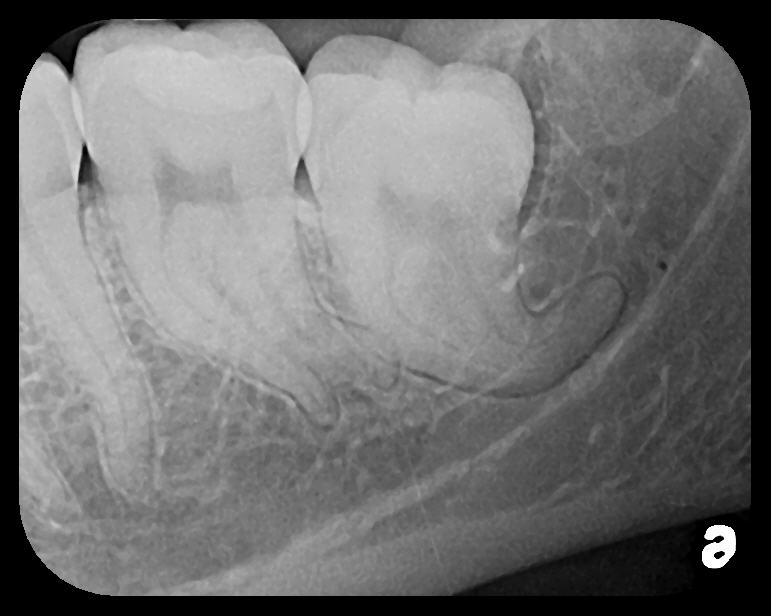

There are two specific types of DIDR sensor systems available to dentists in the marketplace: the hard-wired (HW) sensor and the photostimulable phosphor (PSP) sensor,1,2 also commonly known as phosphor "plates." A desirable feature common to both modalities is the ability to expose either bitewing (BW) or PA radiographic images. The BW radiograph (Figure 1) is usually considered more appropriate for caries detection, whereas the PA (Figure 2) is diagnostic for several different anatomic and pathologic issues.7

Fig 1. Left: Representative PSP BW radiograph with multiple restorative materials of varying radiographic densities. Tooth No. 31 demonstrates deep

caries on mesial aspect beneath the restorative. Radiolucency of carious lesion results from the low relative density of caries compared with healthy

tooth structure. Right: PSP BW radiograph optimized for view of multiple interproximal carious lesions.

Figure 1